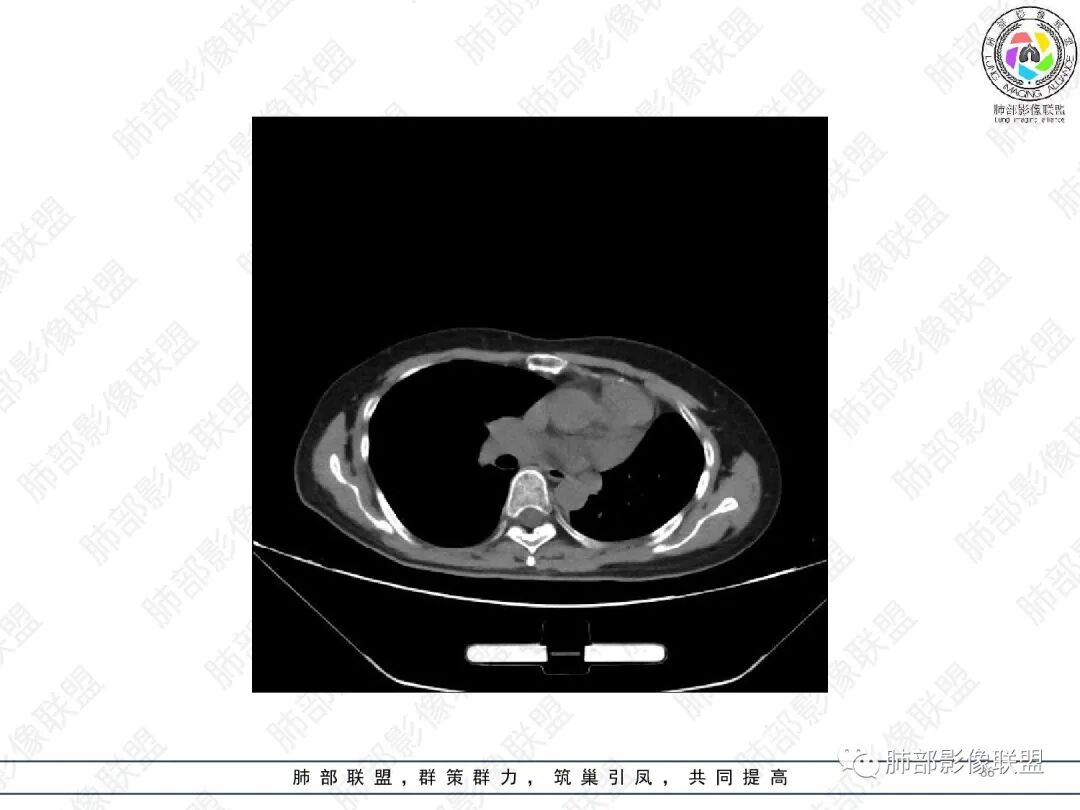

1.中年女性,主因“咳嗽、咳痰半年余”入院,既往史:8年前因左肺病在外院变行左肺叶切除术,诉术后抗结核治疗1年,具体病理等不详。实验室IGE显著增高。

2.胸部CT:右肺上叶及中叶不规则块状影,沿支气管走行方向指套样影,支气阻塞湖嵌塞,腔内可见高密度影。灶周可见磨玻璃,外围见结节影及树芽征。左肺体积缩小,见不规则条索影、胸膜增厚,纵隔牵拉左移。

3.综合分析:结合患者病史及胸部CT主要鉴别ABPA(右肺上叶不规则块影,指套样顺延支气管方向,抗结核治疗1年,肺部病灶仍明显)及继发性肺结核TB(右肺上叶不规则肿块,其可见高密影,边缘模糊,周围卫星灶、树芽征,沿支气管爬行)。

完善气管镜及病理、检验结果(IgE显著增高)等支持ABPA诊断。且给予激素及伊曲康唑治疗后复查胸部CT提示病灶较前吸收,所以诊断明确。